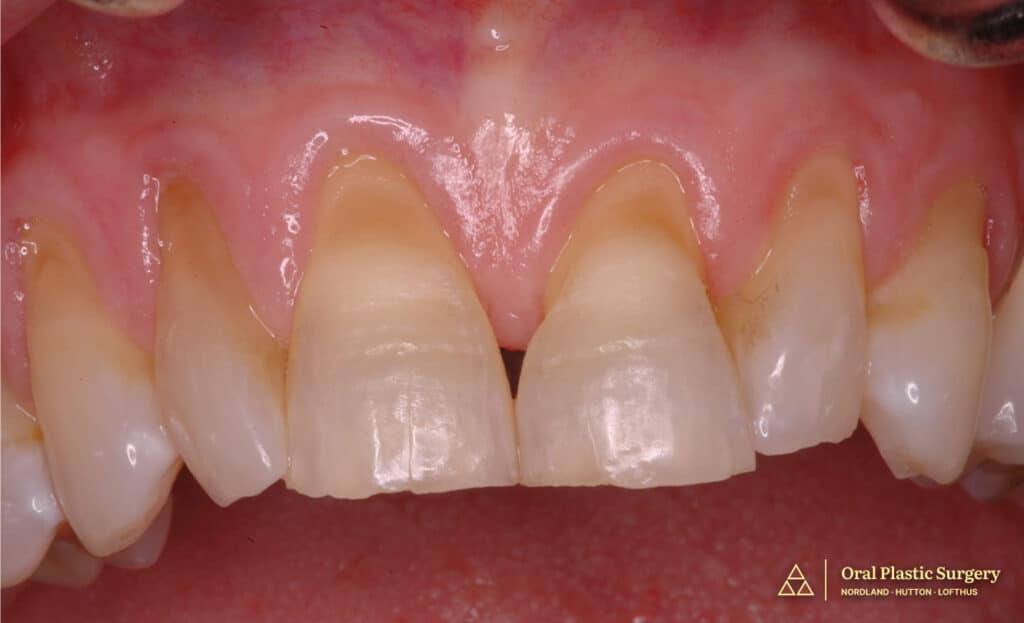

At the time of presentation, RW was in her early 60s and expressed significant concern and embarrassment regarding the appearance of her smile.

Clinical examination revealed gingival recession with exposed, worn, and discolored root surfaces, most notably on the upper and lower anterior teeth.

The maxillary anterior teeth were additionally compromised by chipping, cracks, and discoloration. These changes were consistent with years of cumulative wear and periodontal tissue loss.

The exposed root surfaces not only affected the appearance of her smile but also made it impossible to achieve an optimal esthetic result with restorative work alone.

Initial presentation showing exposed, worn, and discolored root surfaces with chipping and discoloration of maxillary anterior teeth.